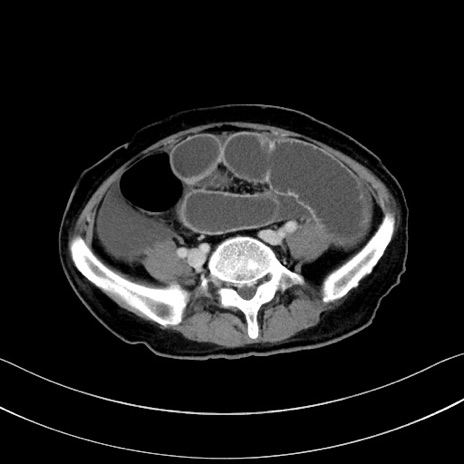

症例28(横断像)

【症例】60歳代男性

【主訴】嘔吐

【現病歴】胃癌にて胃全摘後。食思不振が悪化し、夜中に嘔吐することがある。

【既往歴】胃癌、胃全摘、脾摘、胆摘後

【データ】WBC 5900、CRP 10.56